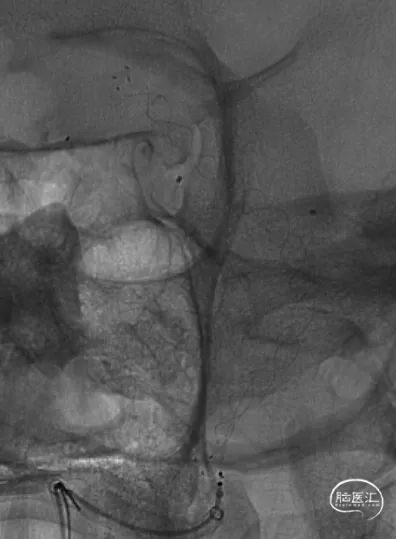

右颈内动脉造影

右侧椎动脉

左侧椎动脉

双侧椎动脉建立通路

经左椎动脉echelon-10微导管预置入基底动脉,经右椎动脉利用双微导丝将headway 27微导管置于右大脑后动脉。

FRED支架释放后,支架CT提示支架贴壁良好

使用25×50、25×50 axium弹簧圈栓塞基底动脉瘤后,使用14×40、10×30、8×30、5×20、3×8 5枚弹簧圈栓塞椎动脉瘤及闭塞左椎动脉末端

经左椎动脉造影,弹簧圈最终完全闭塞左椎动脉V4段,附近的脊髓后动脉保留

经右椎动脉最终造影